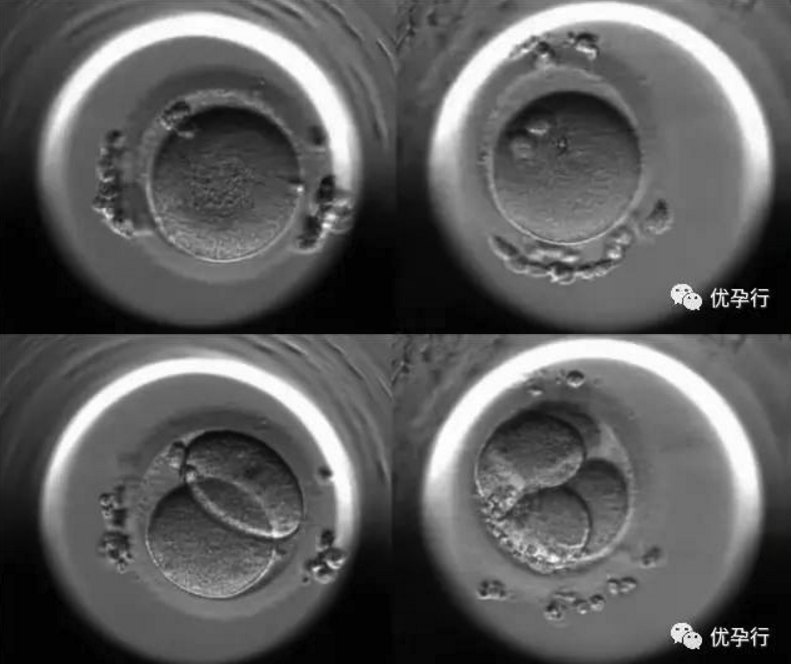

我们来看看胚胎生长的过程:

卵子和精子结合后,显微镜下能看到双原核,这是它们相遇的第一天。

第2~3天,受精卵会分裂成几个至几十个细胞的胚胎。

到了第4天,受精卵被培育成桑葚胚,桑葚胚随后进入高速分裂期,开始加倍分裂。

到了第5天,即成为具有一百多个细胞的囊胚。